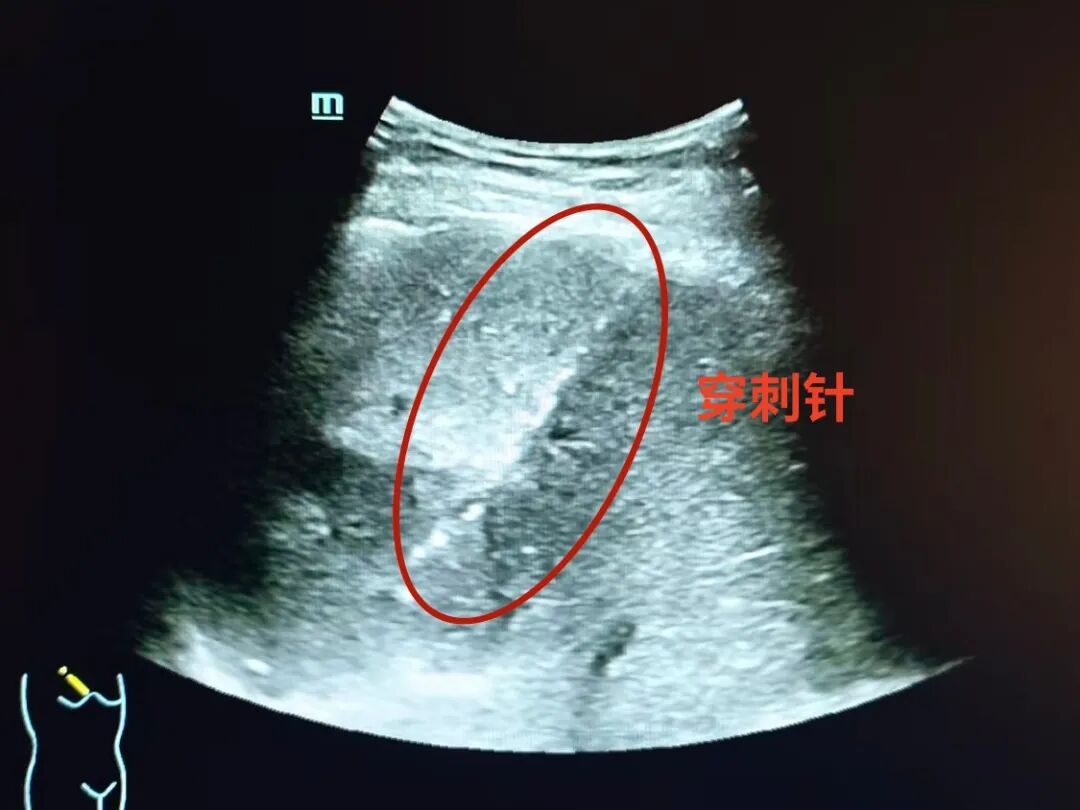

在与患者及家属充分沟通治疗方案、消除其顾虑后,手术顺利开展。石俊泰主任凭借丰富的超声介入经验,在实时影像“导航”下精细操作,精准将细针穿刺进入脓肿部位,顺利引出脓液。整个手术耗时不到20分钟,术中患者无明显不适。